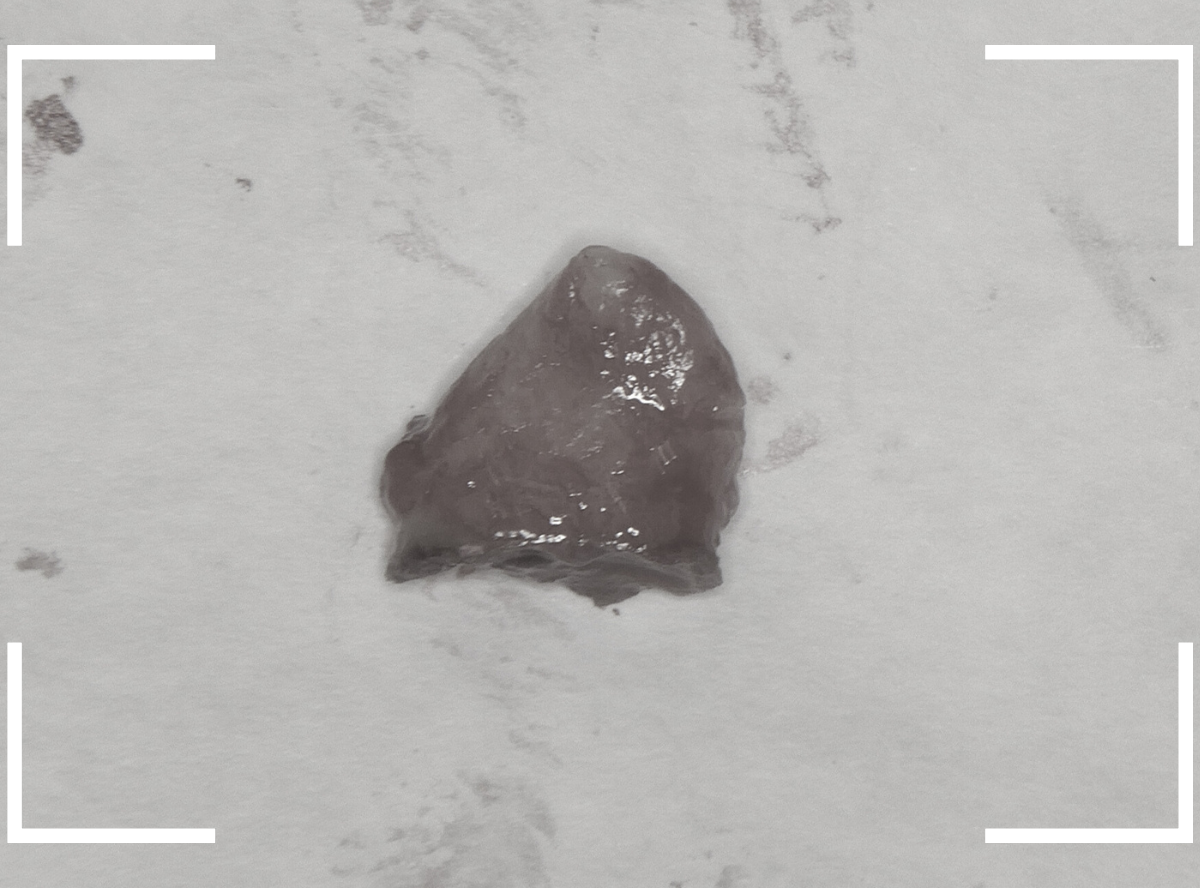

こちらが抜歯後のおやしらずの写真です。

根だけの状態になっていました(残根といいます)が、こちらは苦労なく抜歯できました。